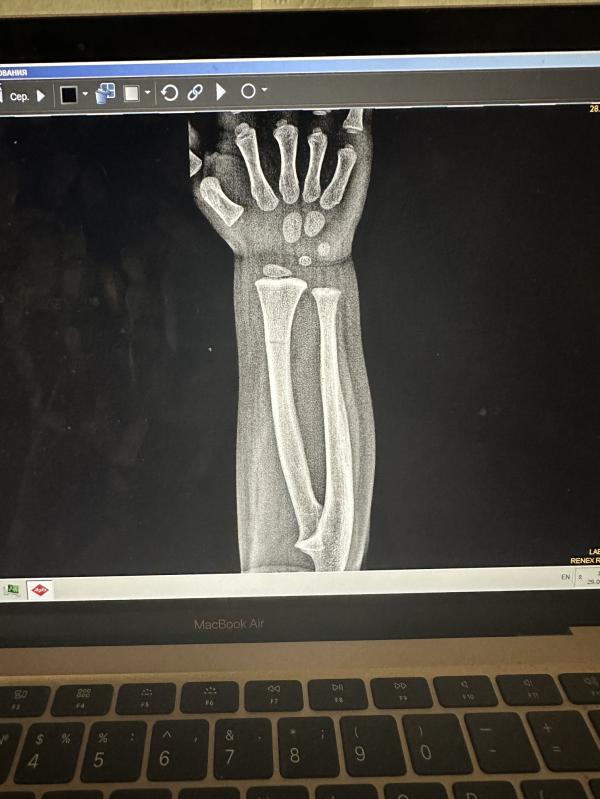

Вы видите две трещины тут на снимке?

Перелом лучевой кости в нижней трети диафиза с небольшой угловой деыормацией. И похоже оч слабо видно и локтевой кости на том же уровне, без смещения. Сломал малыш, но не ужасно, все восстановится довольно быстро . Скорейшего выздоровления!

Две,на одной одна,потом руку развернули и там вторая

Не врач, но вижу трещины. Одна явная, другая чуть выше если присмотреться